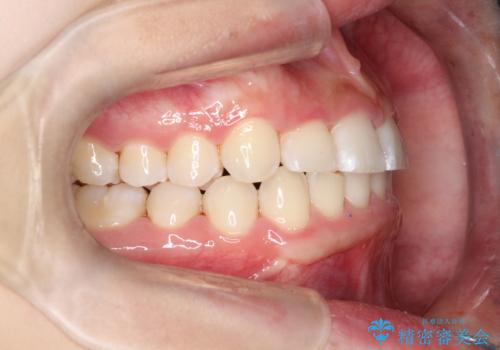

ワイヤー矯正にて下顎前歯の圧下と臼歯部の挺出を効率的に行うことができました。

下顎前歯も綺麗に見えるようになり大変満足していただきました。